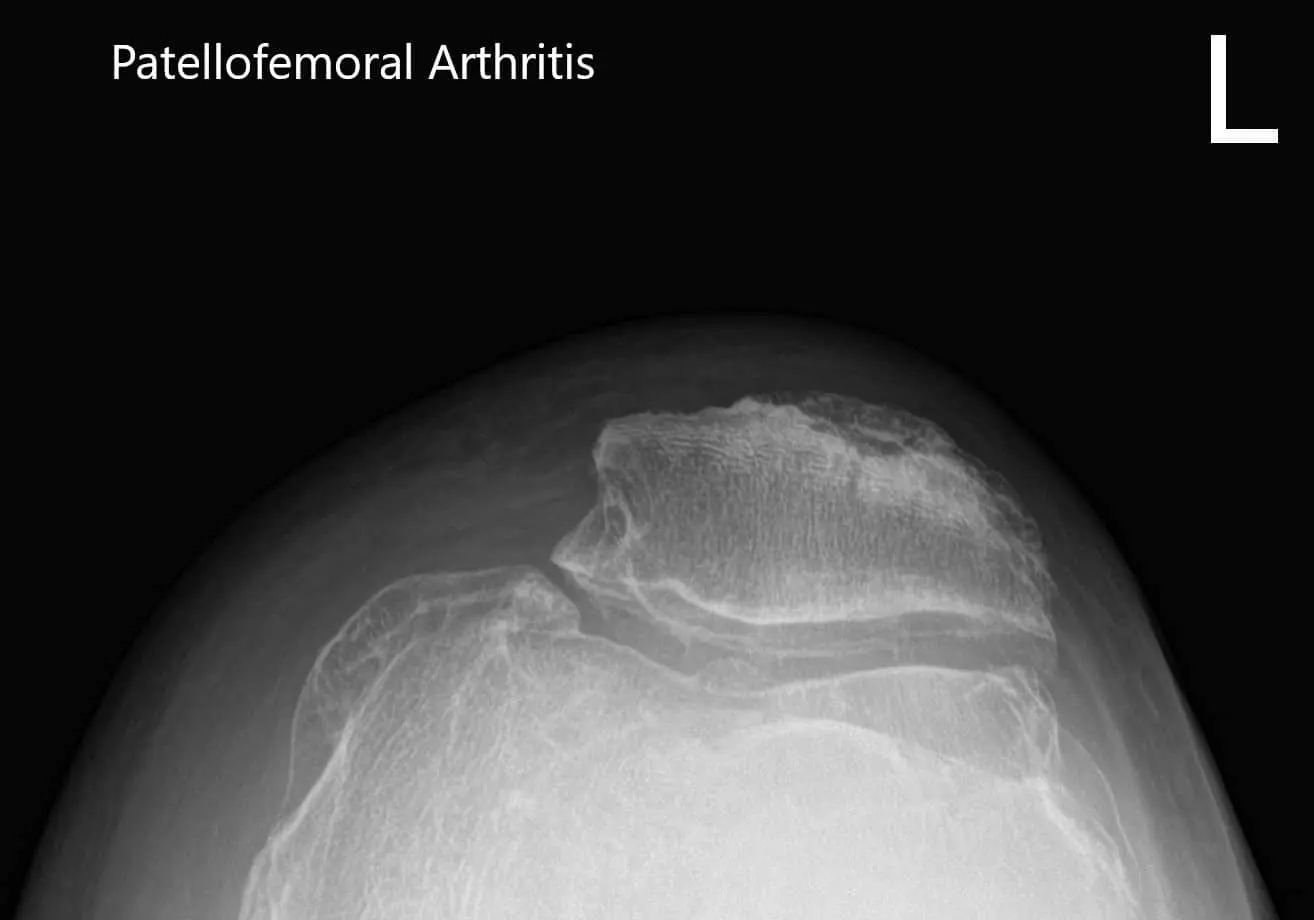

Considering his lifestyle limiting knee pain, various management options including both surgical and nonsurgical were discussed with him at length. He was considered a candidate for custom left knee total replacement. Risks, benefits and potential complications were discussed with him in detail. He agreed to the plan. Imaging studies revealed severe tricompartmental osteoarthritis of the left knee joint.

Preoperative X-ray of the left knee showing AP and lateral view of the knee with a skyline view of the patellaPreoperative X-ray of the left knee showing AP and lateral view of the knee with a skyline view of the patella - img 2Preoperative X-ray of the left knee showing AP and lateral view of the knee with a skyline view of the patella - img 3

Preoperative X-ray of the left knee showing AP and lateral view of the knee with a skyline view of the patella.